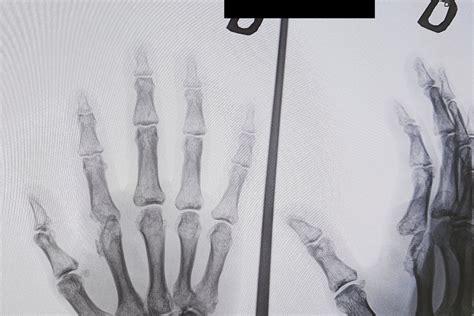

Fizinės apžiūros metu gydytojas apžiūri sąnarius ar jie nėra patinę, paraudę. Bendras kraujo tyrimas - naudojamas įvertinti kraujo forminių elementų (leukocitų, eritrocitų, trombocitų ir kt.) kiekį. Žmonėms, sergantiems reumatoidiniu artritu, dažnai būna padidėjęs eritrocitų nusėdimo greitis arba C reaktyvaus baltymo (CRB) lygis, o tai gali reikšti, kad organizme yra uždegiminis procesas. Siekiant tiksliai nustatyti, koks artritas kamuoja pacientą, gali būti atliekami radiologiniai tyrimai: rentgenograma ar magnetinis rezonansas.

Pažeistų sąnarių rentgeno tyrimas gali būti atliekamas pažeidimo laispniui nustatyti.

Reumatoidinio artrito stadijos pagal rentgeno tyrimą:

- 1 stadija: sergant ankstyvos stadijos RA, aplink sąnarį (-ius) yra uždegimas. Gali būti silpnas sąnarių skausmas ir sustingimas.

- 2 stadija: uždegimas pažeidžia sąnarių kremzlę.

- 3 stadija: uždegimas yra toks stiprus, kad pažeidžiami kaulai. Vargina skausmas. Simptomai labiau išreikšti nei 2 stadijoje.